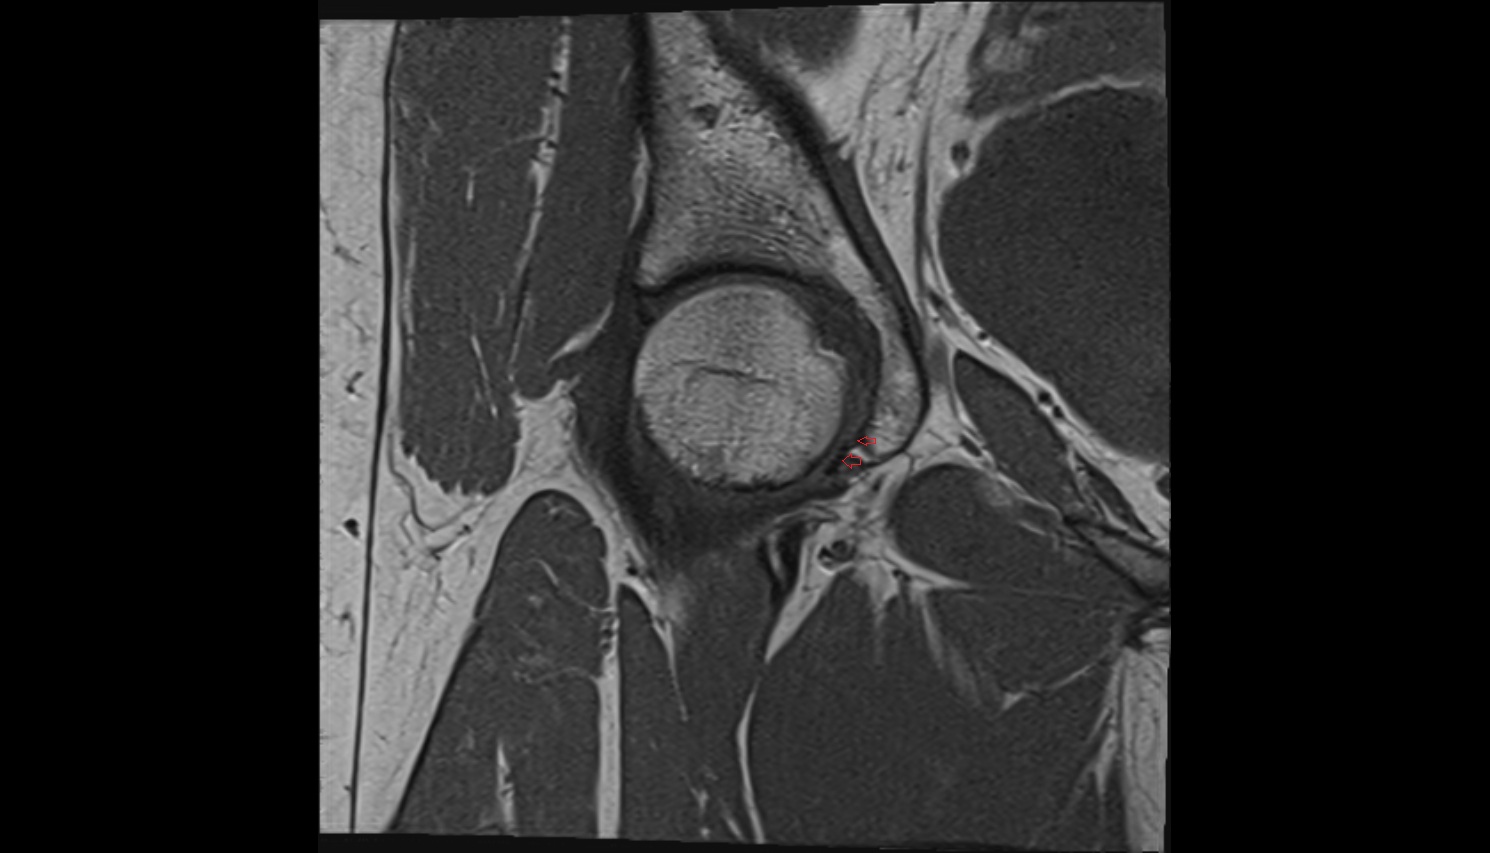

- Obturator artery

- Hip joint